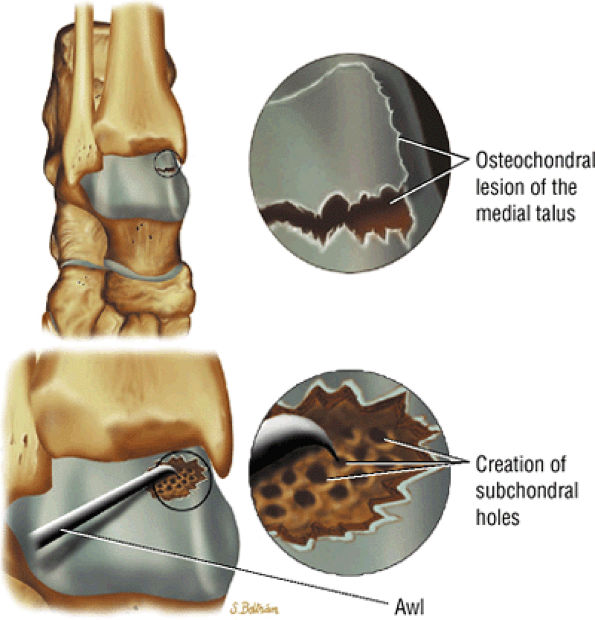

Microfracture (Fig. 5.103).

to determine whether there is enough bone to permit healing, if reattachment with absorbable pins, Kirschner wires, or screws is undertaken. Primary chondral lesions without attached bone are excised, with débridement and drilling or abrading of the base. Loose fragments are either fixed with absorbable pins, Kirschner wires, or screws or are excised with drilling of the base. Displaced lesions are excised, and the base is drilled or abraded if it cannot be reattached.

FIGURE 5.103 ● Microfracture treatment of a medial talar lesion. The microfracture awl is typically introduced through the contralateral arthroscopic portal. The awl is used to create subchondral holes in the bed of the lesion.